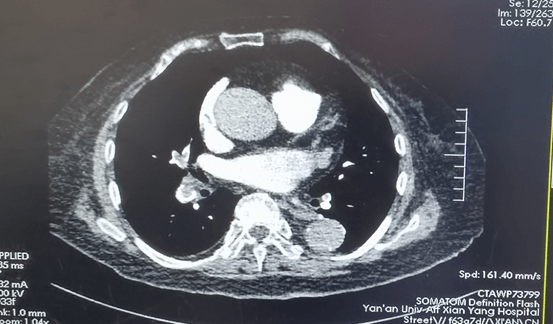

到达我院后,值班医生黄永涛查看患者后,发现她嗜睡状态,查体发现呼吸急促、皮肤黏膜发绀、心动过速、双下肢肿胀,患者血氧饱和度只有46mmHg,血压:135/80mmhg,脉搏:102次/分;黄医生判断患者病情危重,考虑肺栓塞可能,遂请示科主任崔旭辉主任医师。指示:立即完善血气分析、D-二聚体、肺动脉CT造影、下肢深静脉超声等检查等。结果回报D-二聚体显著升高至7.09ug/ml,双侧股总静脉游离血栓形成、双肺多发肺栓塞,进一步证明了肺栓塞的诊断。患者被立即送往CCU呼吸机辅助呼吸并积极抗凝治疗。